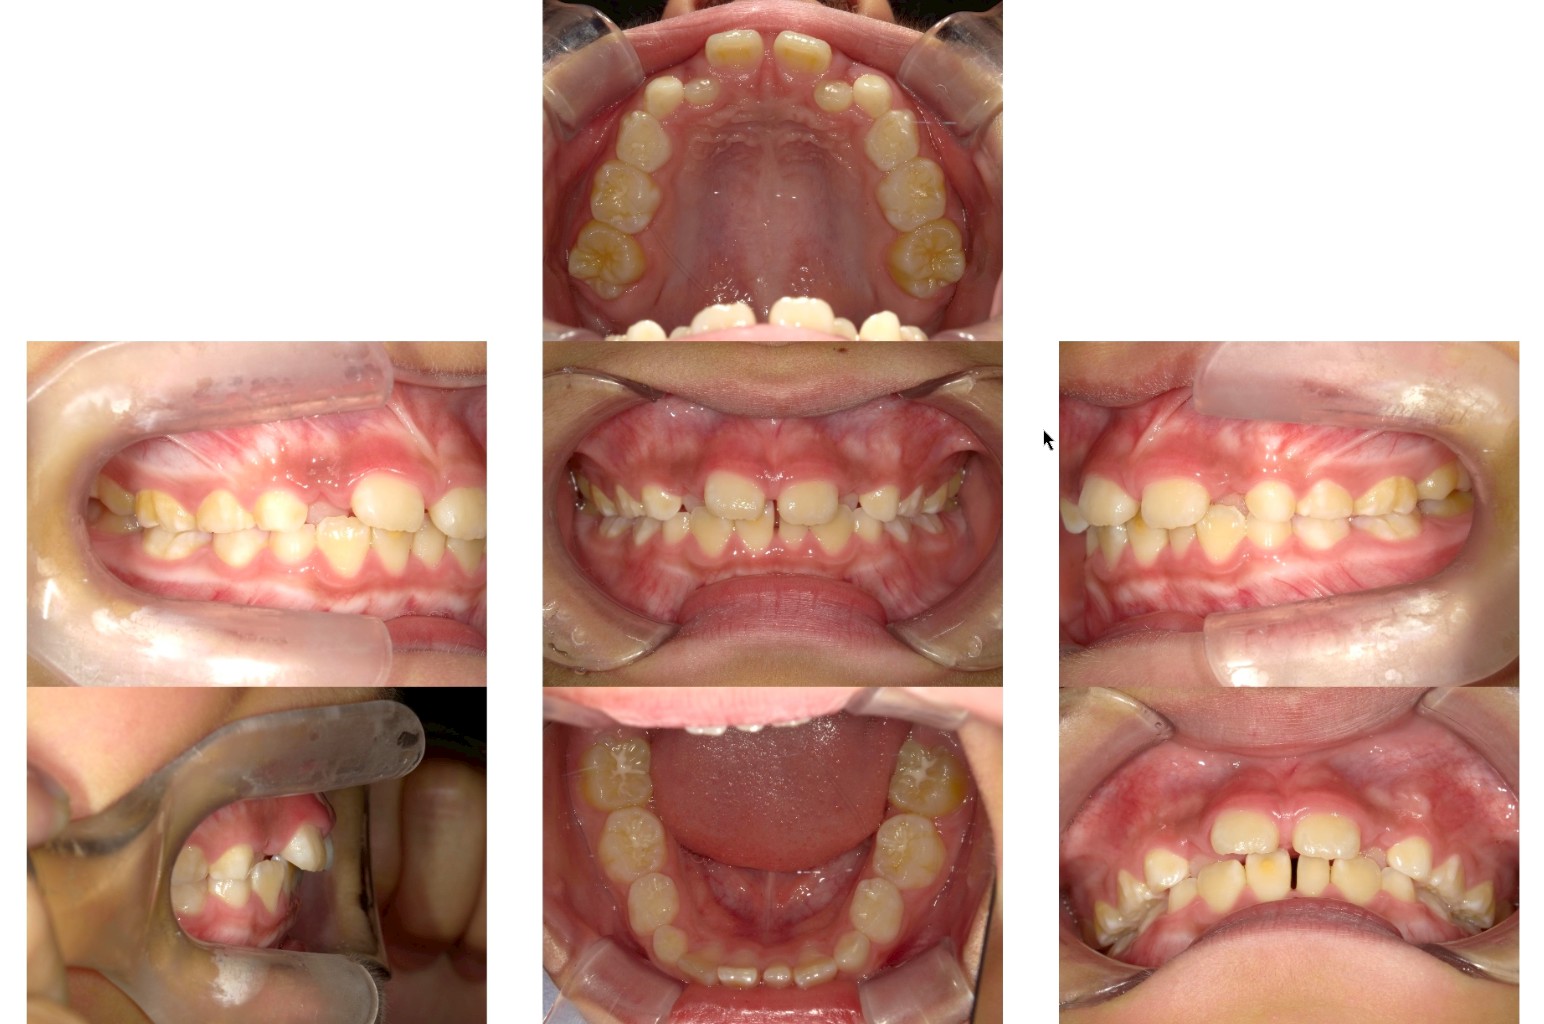

永久歯が乳歯の裏側に生えてきた

通常、永久歯は乳歯の真下から生えてきて、乳歯を自然に押し出すようにして生え替わります。しかし、中には乳歯が抜ける前に永久歯が内側(裏側)から生えてくるケースがあります。これを「二重歯列」とも呼びます。

この現象は、永久歯が予定よりも内側から萌出した場合や、乳歯の根が吸収されにくいことが主な原因です。永久歯の生える方向やスペースの不足、顎の小ささなども関係していることがあります。

前歯の生え変わり期(5〜7歳ごろ)に、乳歯がまだ残っているにもかかわらず、裏側から歯が生えてきているのを見つけたら、早めの歯科受診をおすすめします。上下どちらかの前歯で起きやすく、噛み合わせに影響を及ぼす場合もあります。

放置した場合のリスク

放っておくと、永久歯が正しい位置に移動できず、歯並びが乱れる原因になります。また、乳歯と永久歯が同時に存在している状態が長引くと、噛み合わせや発音に影響することもあります。